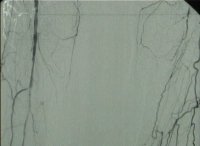

Filmbeispiel: TASC D → offene Rekonstruktion

AVK Stadium IV rechtes Bein, Stadium III linkes Bein mit:

- hochgradiger Arteriosklerose der terminalen Aorta und Beckenstrombahn bds.

- langstreckigem Verschluss der A. femoralis superficialis bds.

- Teilverschlüssen der Unterschenkelarterien bds.

Präoperative DSA des Patienten: